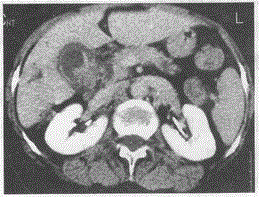

问题 女,57岁,上腹部疼痛3个月,增强后如图最可能的诊断是

选项 A.胆囊炎 B.胆囊息肉 C.胆囊结石 D.胆囊癌 E.胰头癌

答案 D